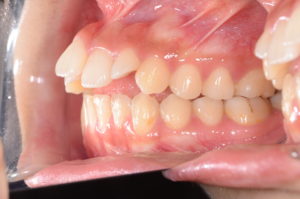

矯正と組み合わせるとさらに効果的

MFTで筋肉の使い方を整えながら、矯正治療で形を正すと効果が長持ちします。

近年は**非抜歯での治療(IPRや顎間ゴム)**も増えており、

自然な口元に仕上げる選択肢が広がっています。